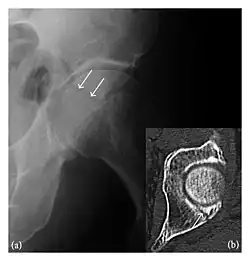

The greater tuberosity of the humerus is also an illustrative location of occult fractures. The osseous injury may follow seizures, glenohumeral dislocation, forced abduction, or direct impaction. They are commonly discovered on MRI in symptomatic patients with suspicion of rotator cuff tear. Coronal images are best suited for detection. They appear as crescentic oblique lines surrounded by a bone marrow edema pattern (Figure 5). The rotator cuff must be inspected since associated ligamentous lesions are common. In the ankle, malleoli and tarsal bones should be checked carefully for any cortical disruptions and radiolucent lines that may reveal a fracture. Awareness of the exact location of the pain will help direct the attention of the interpreter when searching for very subtle signs of fracture (Figure 6).[1]

Figure 6: Subtle anterior talar fracture in a 39-year-old man presenting with ankle pain after a fall. (a) Anteroposterior radiograph shows a subtle oblique radiolucent line through the talus (white arrows). (b) Sagittal CT reformation confirms the presence of an anterior talar fracture with cortical offset (black arrow). Avulsion fractures, which consist of a detached bone fragment resulting from a ligament or tendon pulling away from the bone, may also present with subtle radiographic signs. Tiny osseous fragments near the presumed attachment site of a ligament suggest this diagnosis. Common sites are the lateral tibial plateau (the Segond fracture), the spinal tuberosity of the tibia resulting from anterior cruciate ligament avulsion, and the ischial tuberosity.[1]